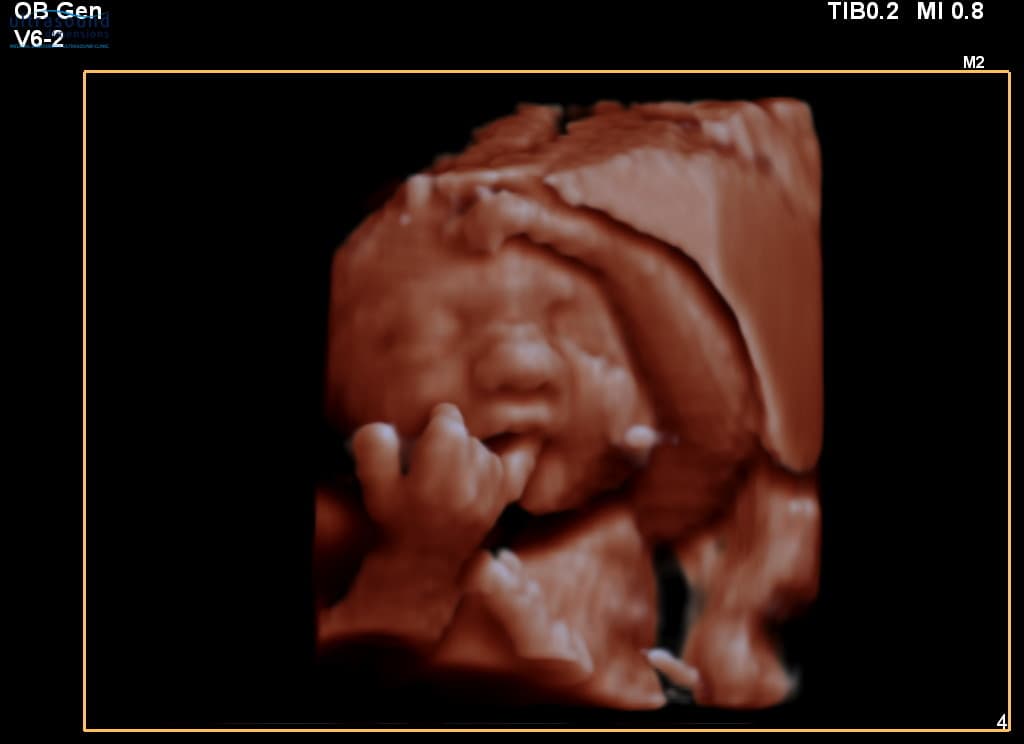

In this video and photos, we are showing you a sample of what you would see at 9 weeks gestation during an early pregnancy scan.

At 9 weeks, your baby is around 2.3cm long (about the size of a grape) and you can typically see:

- The heartbeat - beating strongly at around 170 bpm

- Head and body - distinct but still proportionally large head

- Tiny limb buds - arms and legs beginning to form

- Movement - your baby may already be wriggling!